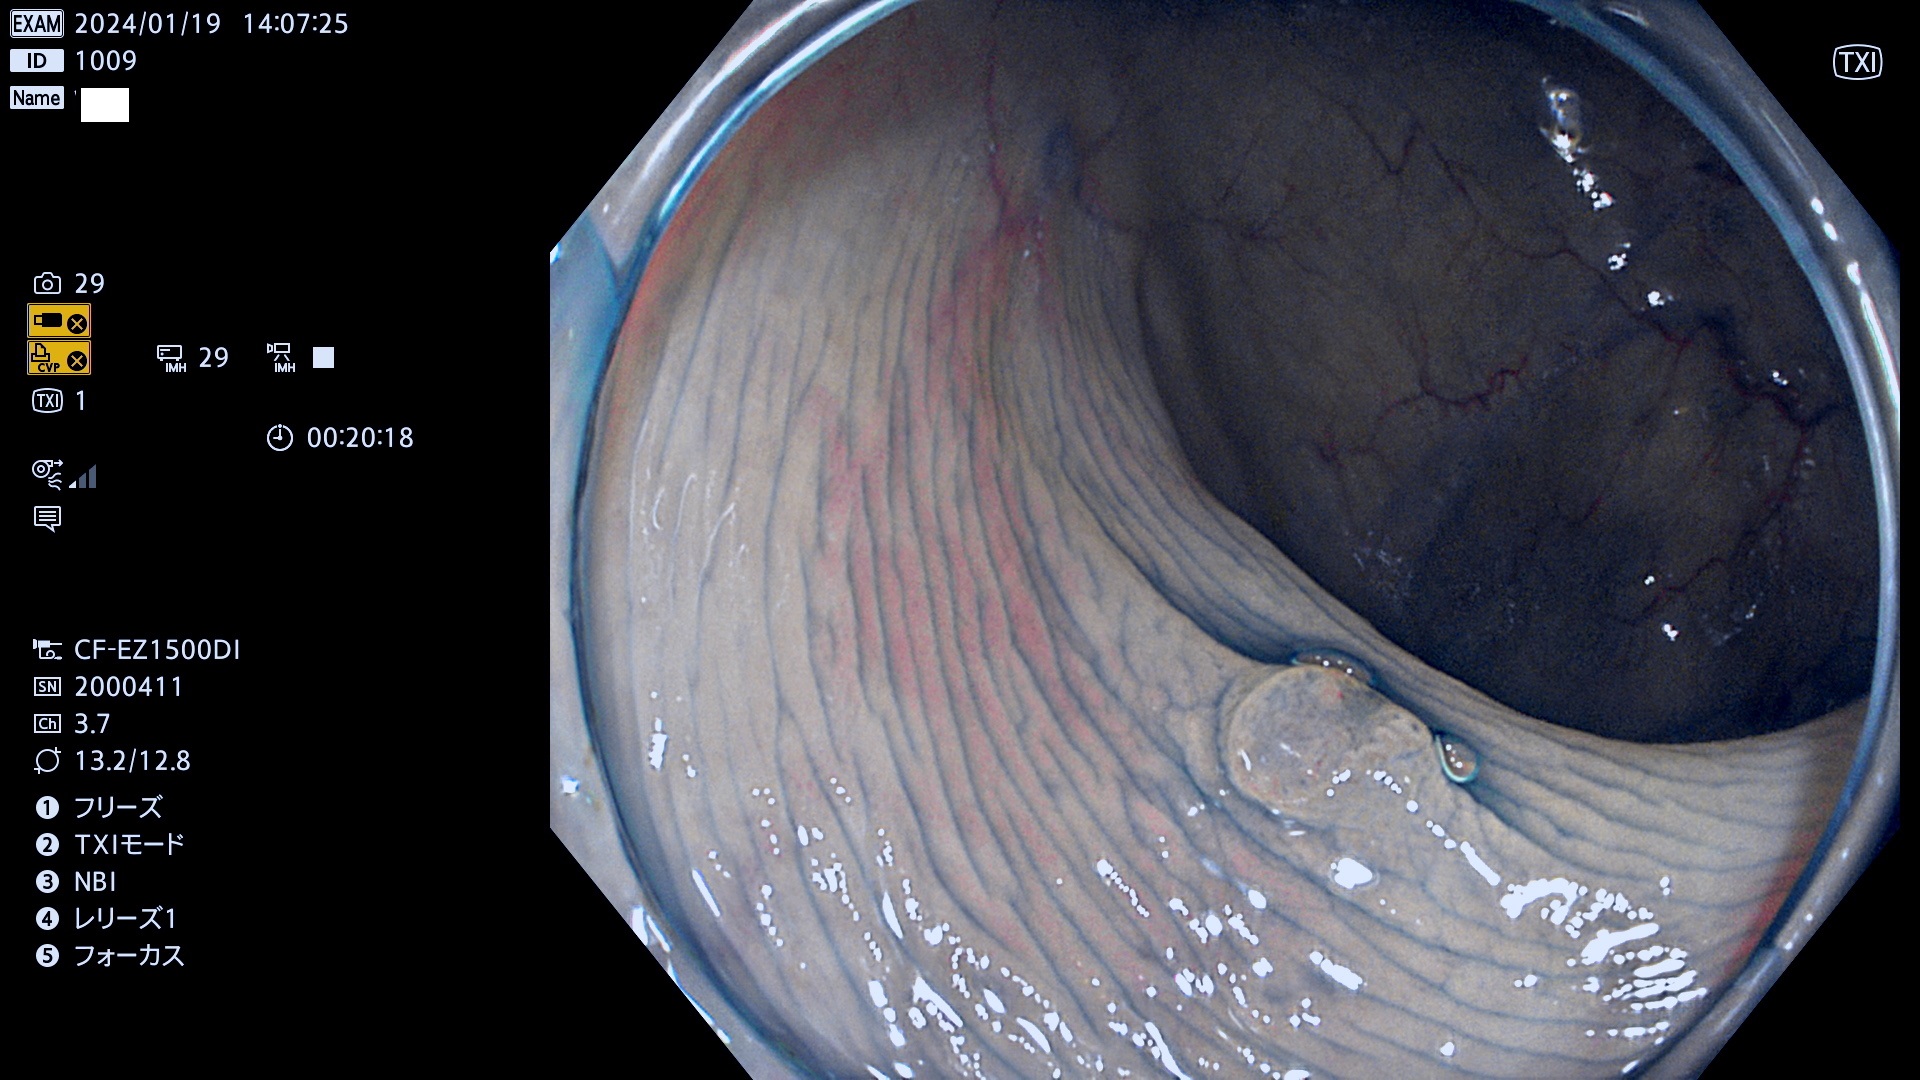

表面型腺腫(Flat Adenoma)の中で、完全に平坦な物をUb、陥凹している物をUcと呼びます。平坦隆起型(Ua)よりも、発見が難しく危険な病変です。

専門的)Uc=De Novo癌? 内視鏡の解像度が低かった時代、このような説もありました。しかし今日の高精度内視鏡では良性の微小なUc型腺腫が日常的に見つかります。私見ですが「Ucこそが多段階発癌(Adenoma-Carcinoma Sequence)のMain Route」と考えます。

毎週の検査(木・金・土・日)に発見されたUb、Uc型・腺腫を、その週の日曜の夜にUPし1週間、提示します。

抽出の対象期間 2024年1月18日(木)〜1月22(月)の5日間(50件の検査)7件